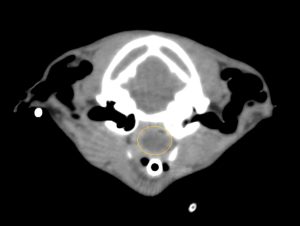

CT検査では、鼻咽頭に左の耳管から続く腫瘤(オレンジ丸)がほぼ完全に鼻咽頭を閉塞していました。また、左の中耳にも病変(青矢印)を認めました。